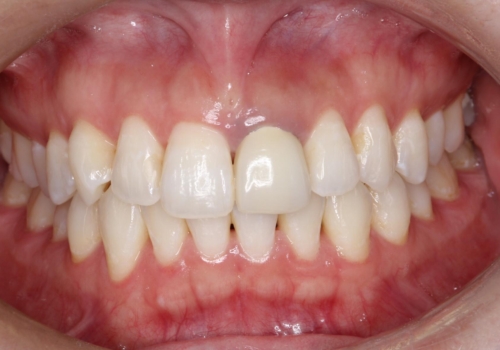

- 左上の前歯の形や色が気になる。

保険の前歯の被せ物のやりかえを希望して来院